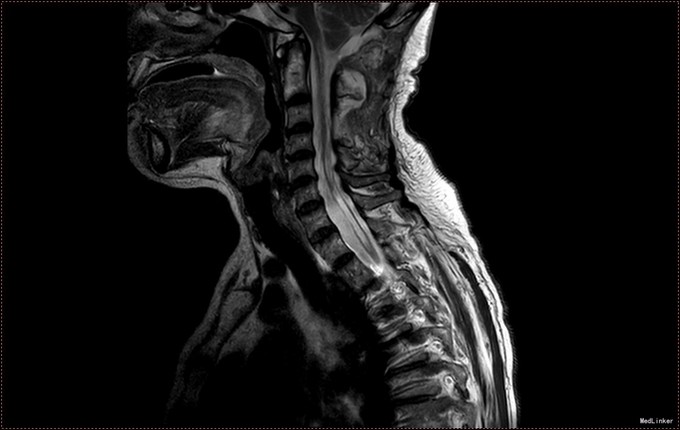

入院查体:神清语明,问答准确,查体合作,精神状态良好。双侧瞳孔等大正圆,D≈3.0mm,双侧眼球活动自如,对光反射灵敏。双下肢肌力减退,肌力三级,肌张力正常。双上肢肌力正常,活动自如。四肢感觉减退,可见多处烫伤瘢痕。双巴氏征(-)。 颈椎MR提示小脑扁桃体下疝畸形,脊髓空洞症(C1-T6);颈椎管狭窄,颈椎间盘膨出(C3-C6)

患者诊断明确,完善术前检查。行枕下减压,扩大修补硬膜,颈髓空洞穿刺。术后予常规治疗。复查颈椎MR提示小脑扁桃体减压充分,脊髓空洞略缓解。但术后3日起发热,行腰穿提示椎管内感染,行腰池引流1周,拔管出院。出院时患者自述左侧肢体麻木感减轻,双下肢肌力较入院好转。